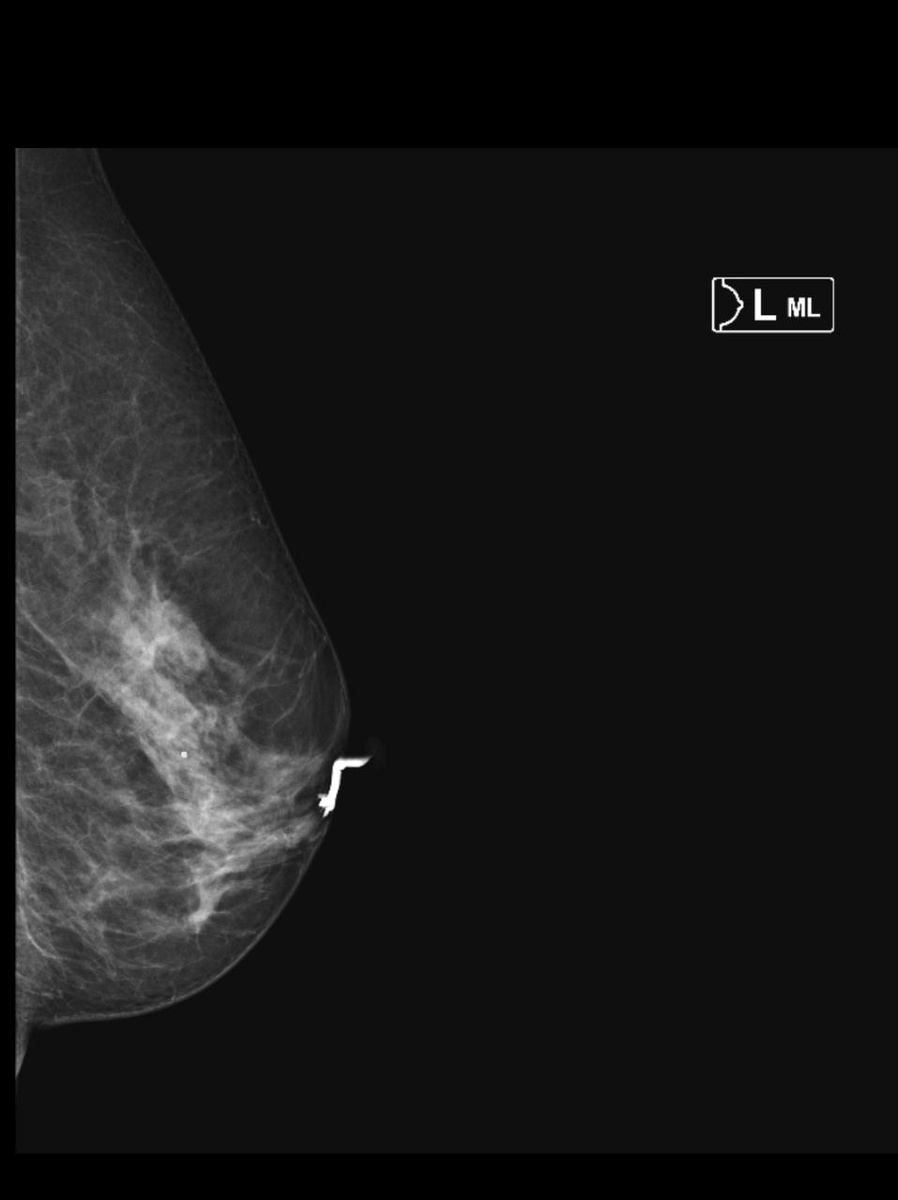

Классическая клиническая картина внутрипротоковой папилломы - обильный выделения из соска соломенного цвета.

На дуктограммах левой молочной железы на границе внутренних квадрантов (близко прилегает к коже) определяется неравномерно заполненный контрастированный магистральный млечный проток, балонно расширенный проток.

Начиная с подсосковой зоны на расстоянии 0,9см, бифурация протока, далее "обрыв" протока - контрастный препарат не определяется, вероятнее за счет внутрипротокового компонента размером от 0,13см в трех ветвях.

Лечение хирургическое в объёме секторальной резекции.